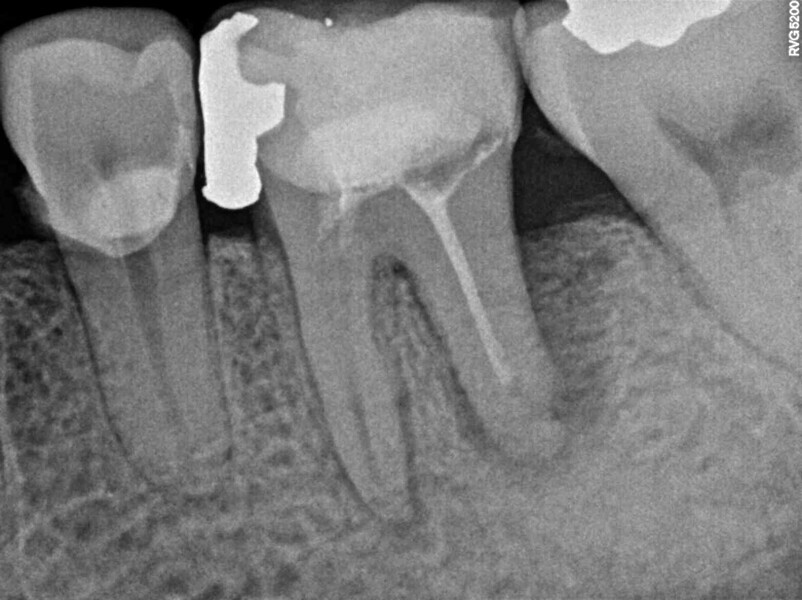

Thereafter, the hemisection procedure was done under local anaesthesia (4% articaine with 1:100,000 adrenaline; Septodont). Under the microscope, an intra-sulcular incision was performed with a #15C blade, and a partial-thickness flap without vertical incisions was raised to observe the furcal area and resect the distal root and its coronal portion with a fissure diamond bur (Figs. 7–9). Curettage of the granulation tissue was performed and the area rinsed with saline, and a synthetic bone graft (DM Bone, Meta Biomed) was placed in the alveolar socket (Fig. 10). Posteriorly, the flap was repositioned and sutured with #6-0 polypropylene material. The sutures were removed seven days later, and the patient was followed up until three months later. At this point, the tissue had healed, and the definitive restoration procedure was initiated. The tooth remnant was prepared, and a fixed bridge with two cast metal extensions cemented on to previously prepared rests on the occlusal aspect of the neighbouring teeth was placed (Fig. 11).

One year later, the restoration was performing well and the patient was asymptomatic. Radiographs and a CBCT control scan showed complete bone healing. On the periapical radiograph, the tooth showed a healthy periodontal ligament and no signs of failure in the restoration (Fig. 12). The cross-sectional, axial and coronal views of the CBCT scan showed good bone width and height and no pathological findings (Figs. 13–16). The oclusal scans and clinical images showed good adaptation of the new restoration and a healthy gingiva (Figs. 17–20).